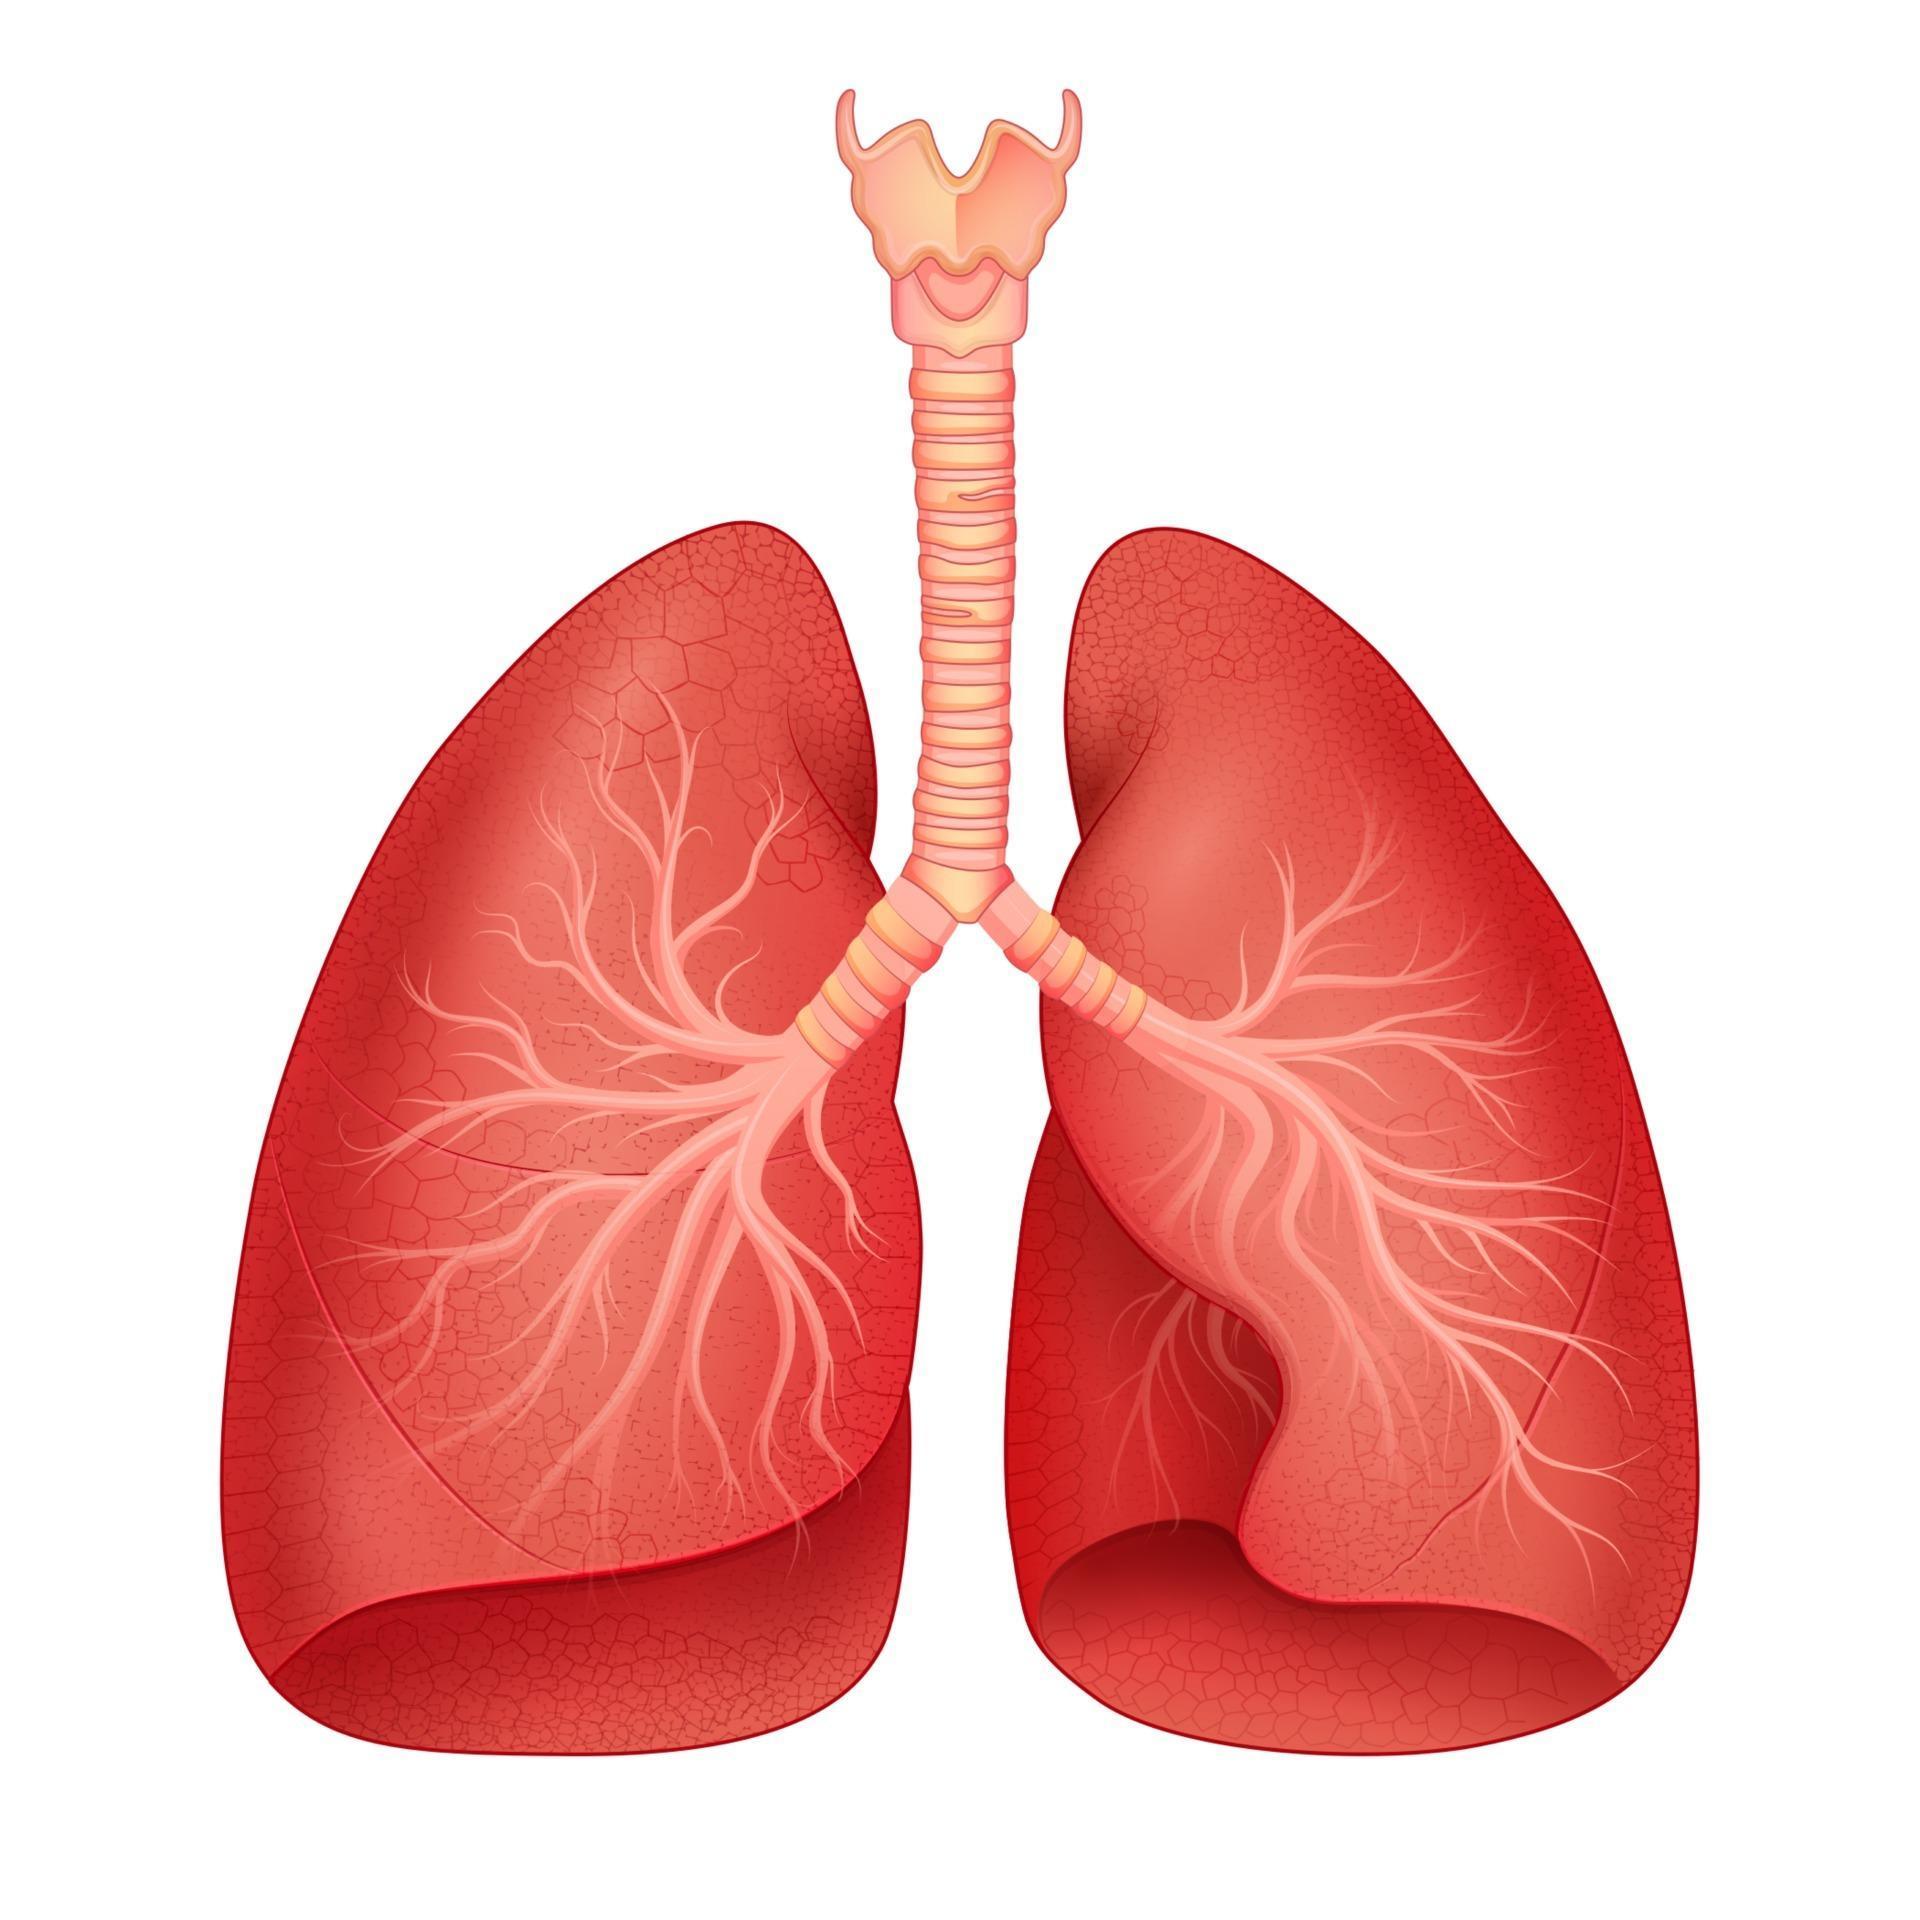

Lista es una colección y muestra de imágenes sobre imagenes de pulmones sanos y enfermos realizada por upup.edu.vn. Además, hay imágenes relacionadas con imagenes de pulmones sanos, imágenes de pulmones sanos, radiografía de pulmones sanos y enfermos, fotos de pulmones sanos, radiografía pulmones sanos y enfermos, rayos x de pulmones sanos y enfermos, pulmon sano y enfermo, pulmón sano y enfermo . Para más información, consulta a continuación.

imagenes de pulmones sanos y enfermos

Posts: imagenes de pulmones sanos y enfermos